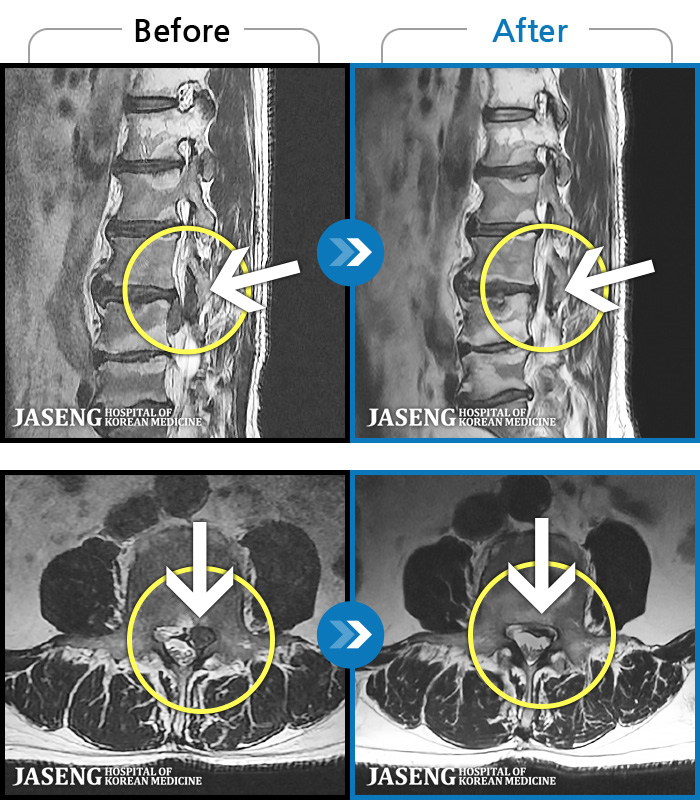

MRI ġ

1,237 MRI ũ ʸ Ȯϼ.